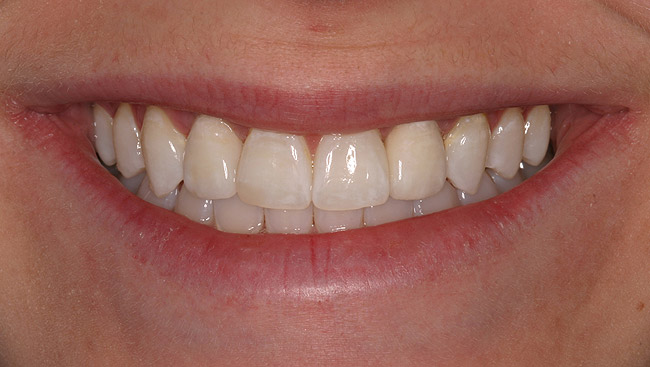

Figure 5a  Congenitally missing lateral incisors. Postorthodontic therapy, prior to implant placement.

Figure 5a

Figure 5b  Congenitally missing lateral incisors. Postorthodontic therapy, prior to implant placement.

Figure 5b

Figure 5d  Completed, porcelain-fused-to-gold implant restorations, custom gold abutments, lingual-set screw-retention, Kerr Extrude¬Æ light-body crown-abutment seal.

Figure 5d

Figure 5e  Completed, porcelain-fused-to-gold implant restorations, custom gold abutments, lingual-set screw-retention, Kerr Extrude¬Æ light-body crown-abutment seal.

Figure 5e

Figure 5f  Completed, porcelain-fused-to-gold implant restorations, custom gold abutments, lingual-set screw-retention, Kerr Extrude¬Æ light-body crown-abutment seal.

Figure 5f

Figure 5g  Completed, porcelain-fused-to-gold implant restorations, custom gold abutments, lingual-set screw-retention, Kerr Extrude¬Æ light-body crown-abutment seal.

Figure 5g